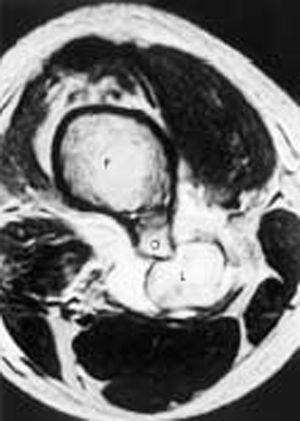

Pruebas complementarias. Se realizó una radiografía lateral del fémur derecho (fig. 1) que mostró la exostosis asociada a un aumento del espesor de las partes blandas no visualizado en las placas de meses anteriores. Se practica un estudio ecográfico (fig. 2) de la zona que demuestra una lesión hipoecoica redondeada, de 5 cm de diámetro aproximado, en relación con la arteria poplítea con flujo arterial turbulento en su interior, confirmada con Doppler color y pulsado. Ante la sospecha diagnóstica se solicitó una RM (fig. 3) que demostró la lesión quística, con zonas de vacío de señal por flujo en su interior, relacionadas con el extremo distal del osteocondroma.

Figura 3.RM de la rodilla derecha. Secuencia axial potenciada en T2*. Lesión redondeada (L), hiperintensa en íntima relación con el margen posterior del osteocondroma (O) femoral (F). Edema de la grasa de alrededor.